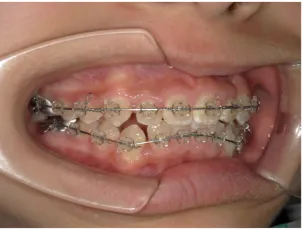

治療中③中1:非抜歯治療の診断で、上顎に歯の生えるスペースをつくるため上顎左右6をプレートで遠心移動し、隙間ができた時点

マルチブラケット法へ移行します

*マルチブラケット法移行前

*マルチブラケット法移行後

| 行ったご提案・診断内容 | 生え変わりが終わってなくマルチブラケット法による咬合治療には早い時期のため、顔立ちの成長を促す目的で歯列弓(アーチ)の拡大と前歯を並べながら永久歯が生えるのを待ち、咬合治療開始時に再診断で抜歯、非抜歯を最終検討する提案をしました。 再診断時(写真②)、歯列の拡大と上顎前歯の並べ替えはされていましたが八重歯となったため抜歯、非抜歯を検討しました。 口元は特に問題がなく非抜歯で八重歯を改善するためのスペースを作ることが可能なため非抜歯治療を提案しました。 治療は、 ・拡大および上顎左右6を遠心移動させてスペースを作る 予定装置 |